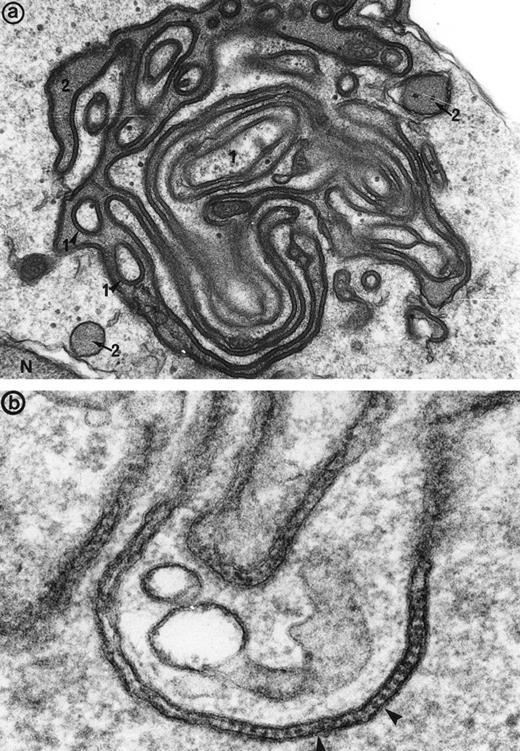

A positive immunogold labeling for immunoglobulin gamma chains was specifically detected along the synartesis, indicating that immunoglobulin could be the responsible agent for the synartesis. Moreover, the observation of a positive reaction only for the gamma chains and not for the mu chains suggested that the immunoglobulin located within the synartesis was an IgG. Finally, immunolabeling for the immunoglobulin light chains kappa and lambda showed that only kappa chains were detected in the synartesis, whereas lambda chain labeling was consistently negative. This observation was evidence for the monoclonal nature of the IgG. Knowing that both patients had a serum monoclonal IgG kappa, the IgG detected in a synartesis seemed to be identical to the one in their serum.

Thus, immunogold labeling showed that the monoclonal IgG, gamma, and kappa chains were present all along these abnormal junctions (Fig6), but labeling was only rarely observed on the parts of the erythroblast membranes that were not physically involved in the junctions.

Immunogold labeling for gamma chain (and kappa chain, not shown) is positive along the linear junctions of erythroblasts (arrowheads) (a), as well as between glove finger invaginations (b and c), showing that the monoclonal IgG are indeed responsible for the synartesis (Original magnification: [a]: ×55,000; [b]: 55,000; [c]: 45,000).

Immunogold labeling for gamma chain (and kappa chain, not shown) is positive along the linear junctions of erythroblasts (arrowheads) (a), as well as between glove finger invaginations (b and c), showing that the monoclonal IgG are indeed responsible for the synartesis (Original magnification: [a]: ×55,000; [b]: 55,000; [c]: 45,000).

Some plasma cells were also found in the marrow and synthesized the same type of monoclonal immunoglobulin as the one found in the synartesis, such identified by the positivity of immunolabeling for gamma and kappa chains (Fig 7a) and negativity for lambda chains: indeed, plasma cells stained for the same light and heavy chain isotypes as the one found in the serum and synartesis. Immunolabeling for mu, delta, and lambda chains were consistently negative.

(a) Bone marrow plasma cells display immunolabeling for the monoclonal gamma chains in the numerous prominent cisternae of endoplasmic reticulum (er) in patient 2. m, mitochondria, N, nucleus. Original magnification ×30,000. (b) Bone marrow immunogold labeling for CD36: Gold particles outline the erythroblast junctions (arrowheads) where immunolabeling is more concentrated compared with the erythroblast plasma membrane (pm) not involved in the junction. Original magnification ×40,000.

(a) Bone marrow plasma cells display immunolabeling for the monoclonal gamma chains in the numerous prominent cisternae of endoplasmic reticulum (er) in patient 2. m, mitochondria, N, nucleus. Original magnification ×30,000. (b) Bone marrow immunogold labeling for CD36: Gold particles outline the erythroblast junctions (arrowheads) where immunolabeling is more concentrated compared with the erythroblast plasma membrane (pm) not involved in the junction. Original magnification ×40,000.

When bone marrow sections were incubated for the immunodetection of the adhesion receptor CD36, which is a marker present in normal erythroblasts and absent from erythrocytes, some specific labeling was found in the junctions where it was definitely concentrated, compared with the erythroblast surface not involved in the junctions (Fig 7b).